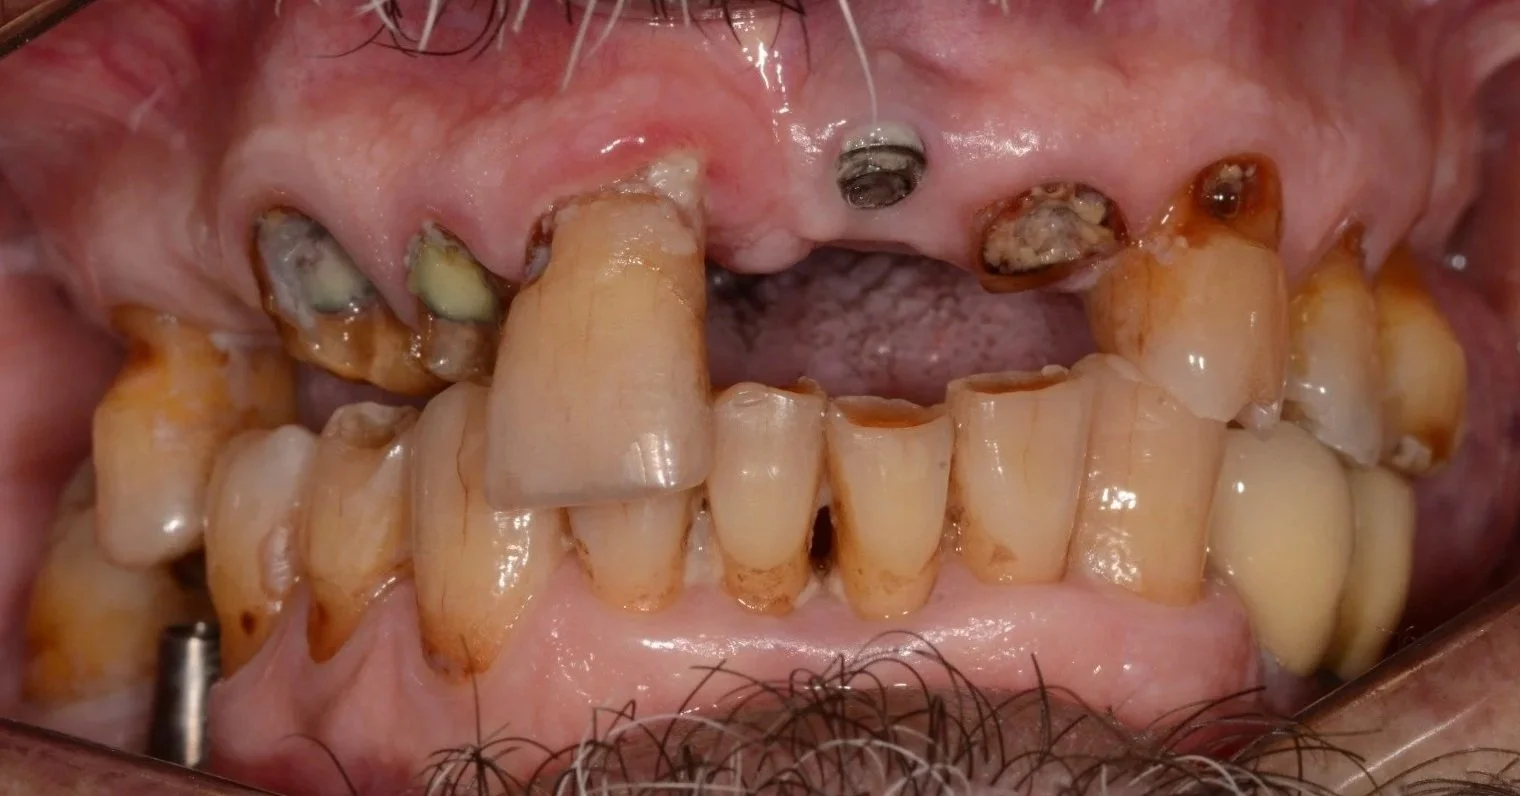

EXAMEN INICIAL: El paciente desea de mejorar su función masticatoria, recuperar su salud oral y lograr una apariencia estética favorable.

DIAGNÓSTICO: Presenta riesgo y actividad de caries, periodontitis estadío II grado A generalizada, brechas desdentadas clase III del sector I y II (de 15-17 y de 25-27) y sector III (de 35 a 37).

PRONÓSTICO: Desfavorable.

Antes